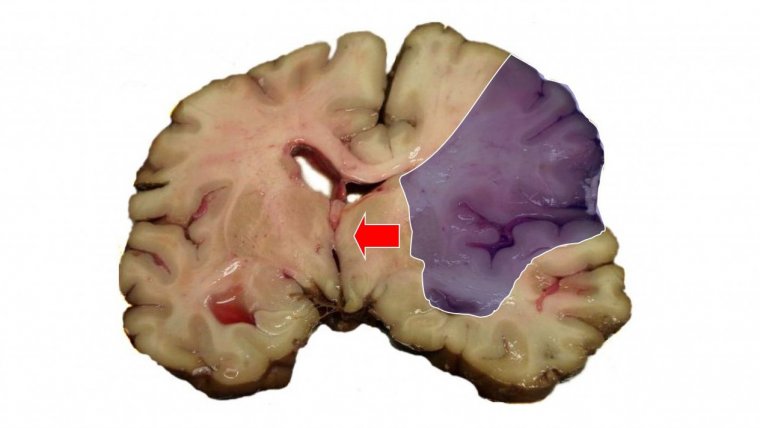

La palabra “ictus” se utiliza para denominar a un tipo de accidente circulatorio que altera el flujo de sangre que se dirige al cerebro. Esto provoca la obstrucción o la ruptura de vasos sanguíneos del cerebro, lo cual a su vez puede causar la muerte de los tejidos irrigados por dichas estructuras, y en consecuencia la alteración o la pérdida de las funciones asociadas.

Existen dos tipos principales de ictus: los hemorrágicos y los isquémicos. Mientras que los primeros son consecuencia de la rotura de vasos sanguíneos, los ictus isquémicos se asocian a la obstrucción de la circulación de la sangre por el cerebro.